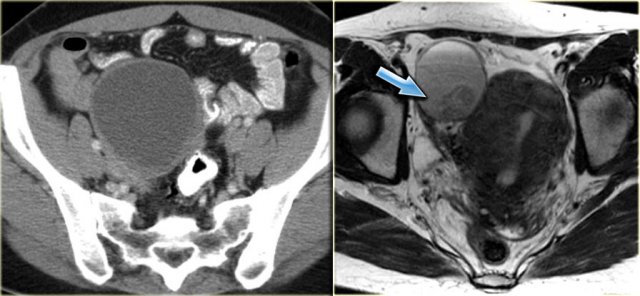

Cystic metastases to the ovaries

While metastases to the ovary are most commonly solid - such as for example Krukenbergs metastases - cystic ovarian metastases do occur.

The CT image shows complex cystic masses in both ovaries.

While a serous cystadenocarcinoma may very well be bilateral, they are more often unilocular than multilocular.

Barely visible is part of a circumferential colorectal cancer (blue arrow).

Clearly visible are cystic implants on the peritoneal reflection (red arrow). These were cystic ovarian metastases of a colorectal cancer. This is an uncommon finding.